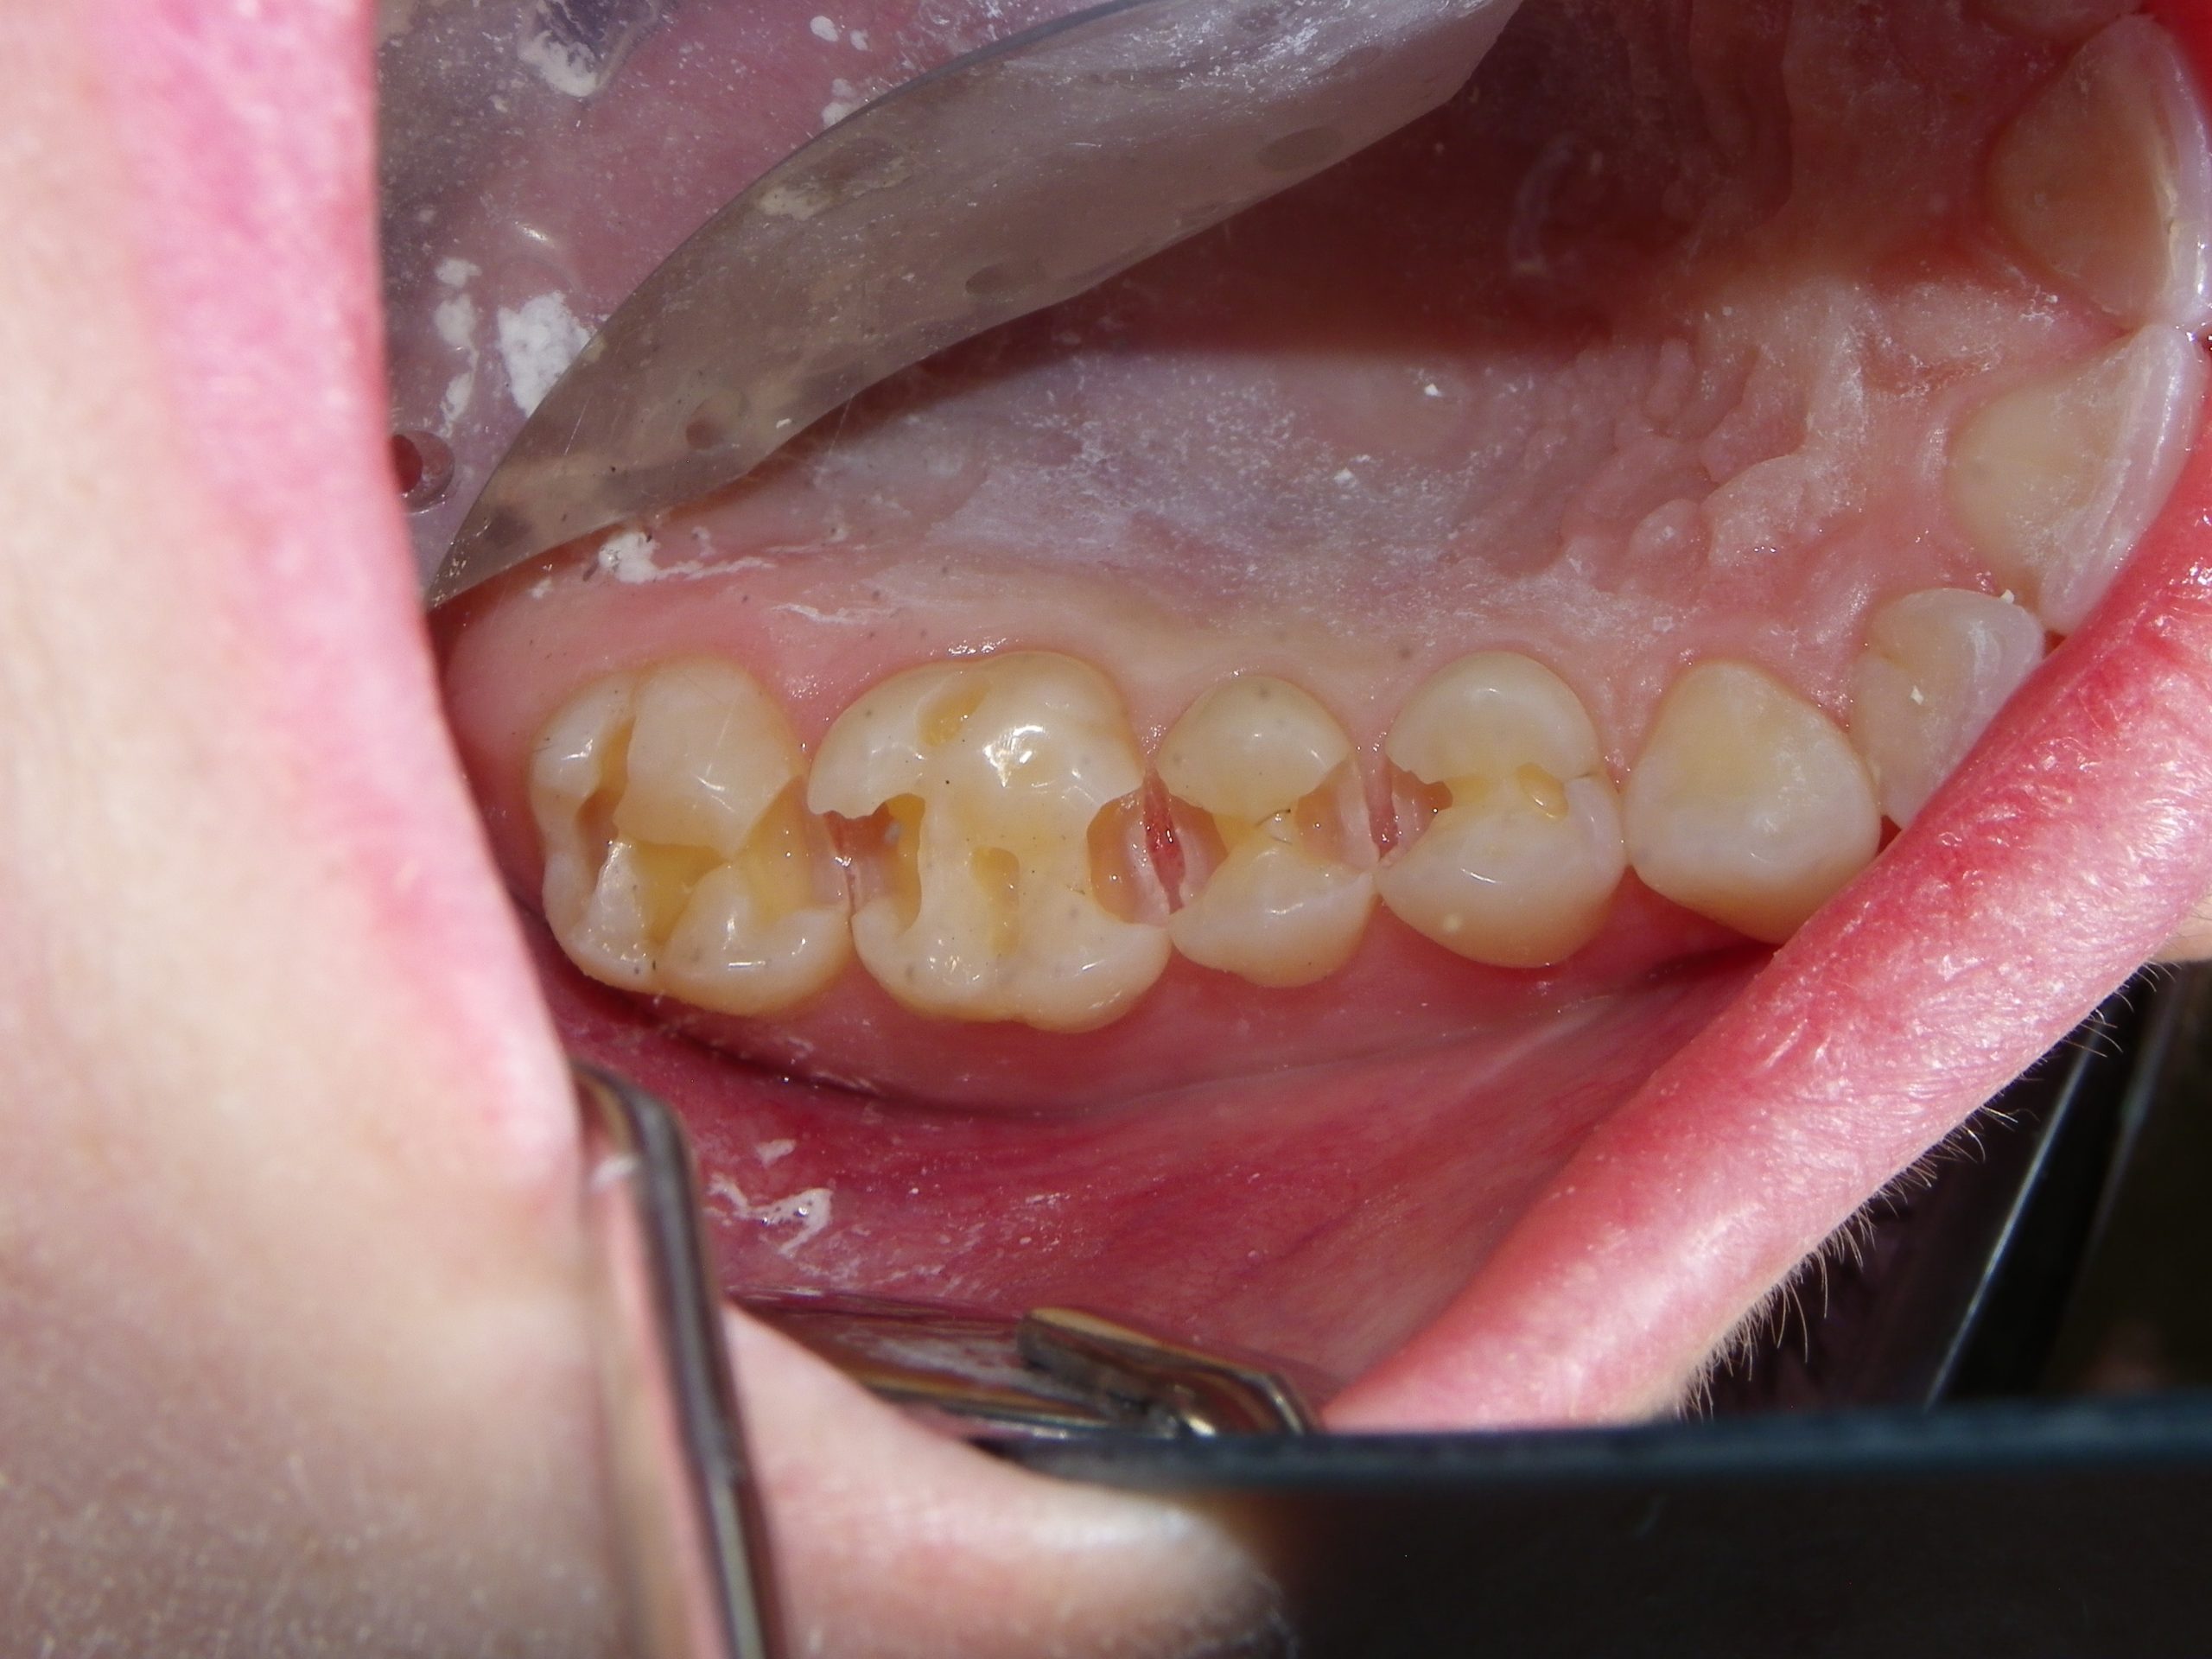

After educating the patient on the decay risks of this behaviour, oral hygiene instruction and a recommendation for a daily fluoride rinse, she can now take action to prevent any new cavities from developing for the rest of her life. There were many areas of decay between other teeth that we elected not to fill due to their small size, and hopefully they remain arrested / remineralized! (Aluminum oxide Air abrasion via PrepStart, 32% Phosphoric acid etch with Benzalkonium Chloride and AllBond Universal adhesive from Curion, Esthet-X Flowable A2 liner from Dentsply, Simplishade Medium resin core from Kerr).